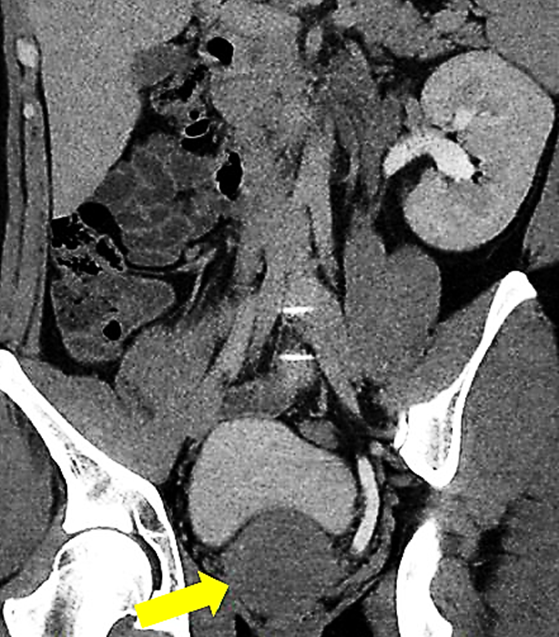

Computed Tomography (CT)

• Useful for:

• Confirming renal agenesis

• Visualizing seminal vesicle cyst (well-defined, fluid-attenuation mass)

• Assessing mass effect on adjacent organs

1. This case involves a 68-year-old male patient diagnosed with stage IIIA chronic kidney disease (CKD), who has a congenitally absent left kidney.

2. He presented with resistant hypertension and elevated serum creatinine levels.

3. A computed tomography (CT) scan was performed.

Findings:

There is congenital absence of the left kidney. Additionally, the left seminal vesicle is also absent.